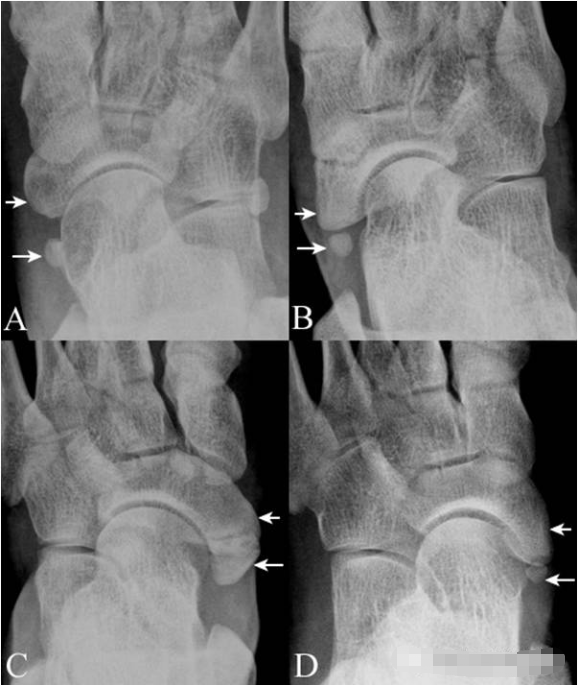

11.外胫骨:舟骨粗隆(短箭)的后内侧可见形态不一的外胫骨(长箭),A图为 I 型, B图为 II 型, C图为 III 型。D图示在明显突出的舟骨粗隆后见外胫骨( II 型),融合后即为 III 型。外胫骨需与舟骨撕脱骨折鉴别,临床表现和周围软组织改变可提供依据。